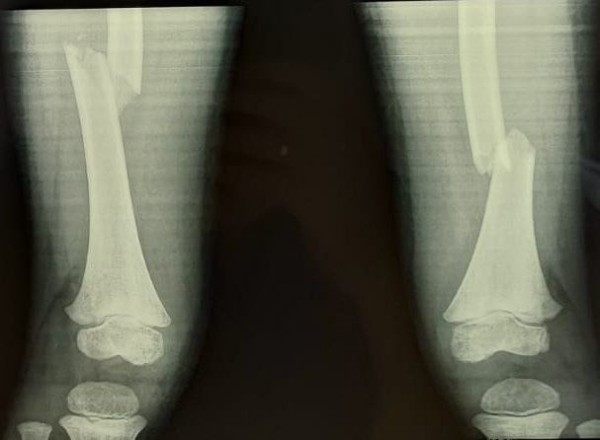

— Здесь беда была в чем. Шейка бедра была сломана — а это то, за счет чего мы вообще опору даем и благодаря чему есть движение в тазобедренном суставе. Плюс оскольчатый перелом был в дистальном отделе, где коленный сустав. Было большое количество отломков, нужно было все застабилизировать. Был риск несращения, так как идет размозжение тканей вокруг. Был велик риск асептического некроза — когда кости не приживаются, — вспоминает врач травматолог-ортопед Максим Перфилов.

Ногу практически собирали по частям. Сначала в неотложном порядке одномоментно выполнили остеосинтез аппаратом Илизарова многооскольчатого перелома дистального отдела бедра, а затем выполнили полиосинтез шейки одноименного бедра.